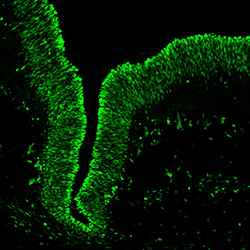

An anatomical analysis of the developing human midbrain from 6 post-conceptional weeks (PCW) to 22 PCW reveals increased tissue complexity, characterized by the emergence of dopaminergic nuclei, as highlighted by immunofluorescence analysis for tyrosine hydroxylase (TH).

MAP2

7PCW human midbrain

TH

Merged